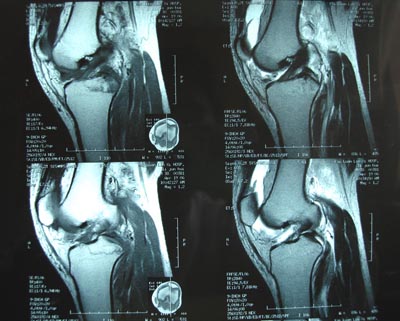

标题: 现将mri结果公布

手术证实是后交叉韧带胫骨附着处撕脱骨折。

术中用可吸收螺钉固定。